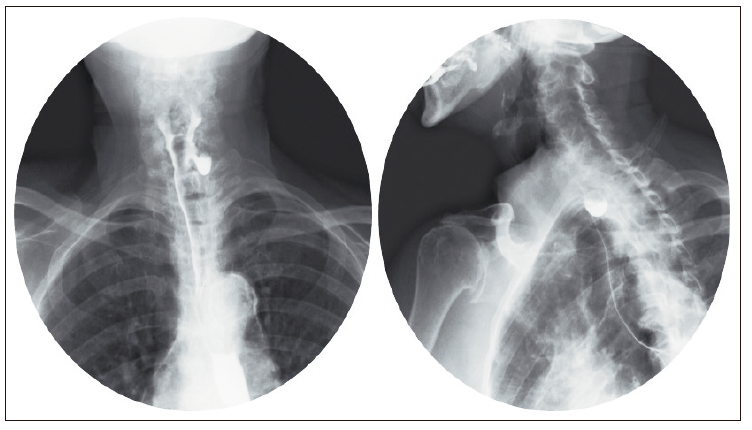

Paciente femenina de 83 años, con antecedentes de cardiopatía isquémica, hipertensión arterial y dependencia funcional, quien ingresó por cuadro agudo de melenas, náusea y anorexia. Al ingreso al servicio de urgencias se encontraba sin signos de choque, con tacto rectal positivo para melena y documentación de anemia sin criterios de transfusión. Se realizó esofagogastroduodenoscopía, que reportó dos desgarros mucosos cardiales, uno de ellos con signos de sangrado reciente, por lo cual se realizó hemostasia con clip, sin complicaciones. Adicionalmente, se halló un divertículo en esófago cervical, inicialmente clasificado como divertículo de Zenker, por lo cual se indicó caracterización por medio de radiografía de vías digestivas altas (Figura 1).

Figura 1. Radiografía de vías digestivas con paciente en posición

erguida: las radiografías obtenidas en proyecciones frontal y oblicua muestran opacificación diverticular en

nivel lateral izquierdo en esófago cervical, justo a nivel inferior del músculo cricofaríngeo con cuello de

4 mm y longitud de 20 mm